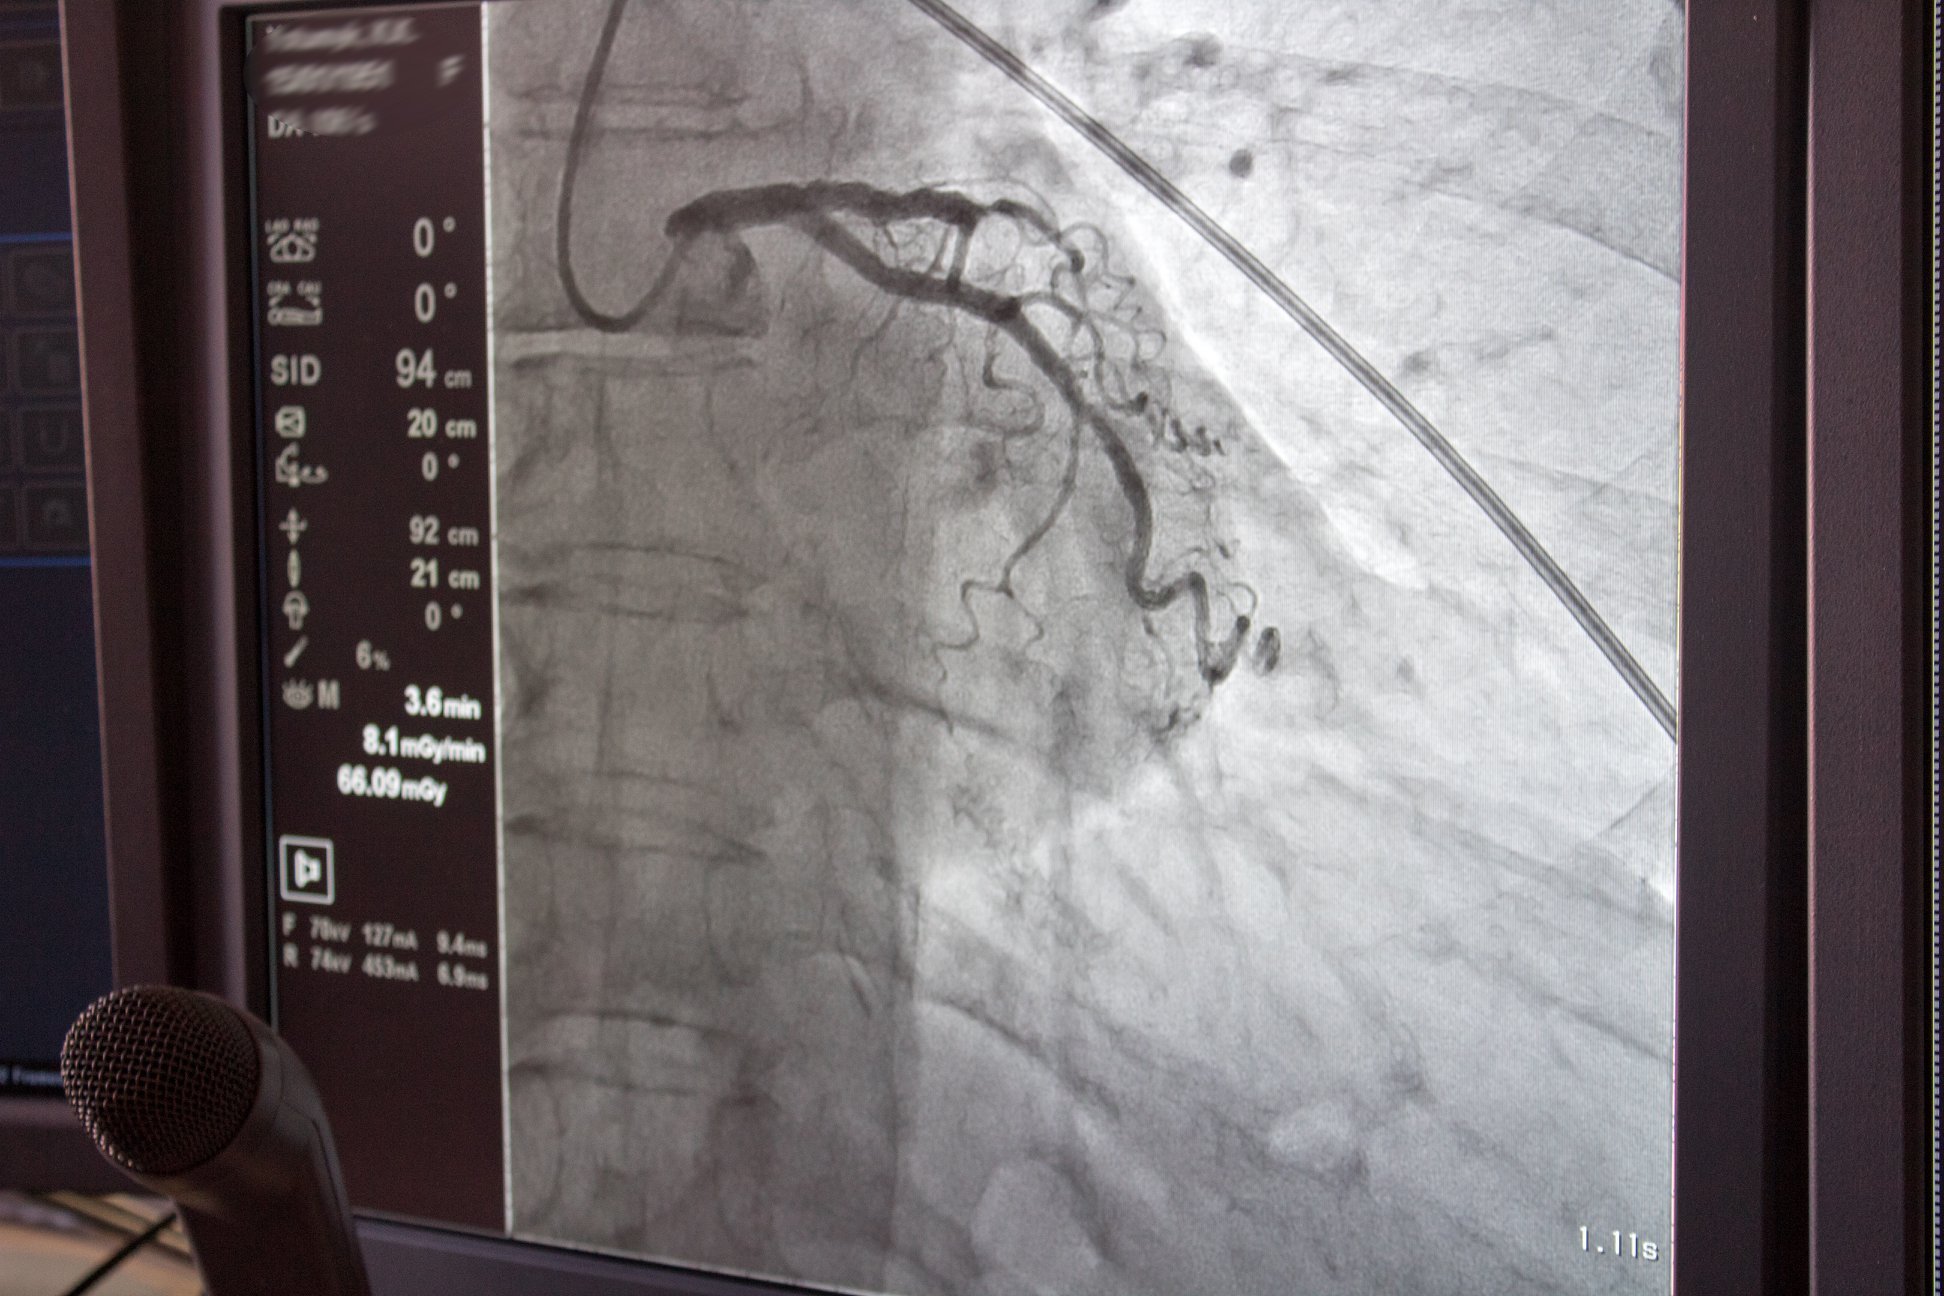

Те, що відбулося вчора, медичною термінологією звучить так: три коронографії та одне стентування проксимального відділу передньої міжшлуночкової гілки лівої коронарної артерії (ПМШГ ЛКА). А звичайною мовою — проведено діагностику трьом волинянам віком від 35-ти до 65 років. А одному — 41-річному — після перенесеного понад тиждень тому інфаркту міокарда (про який, до слова, він навіть не знав) поставлено стент, що дозволить людині повернутися до звичного способу життя.